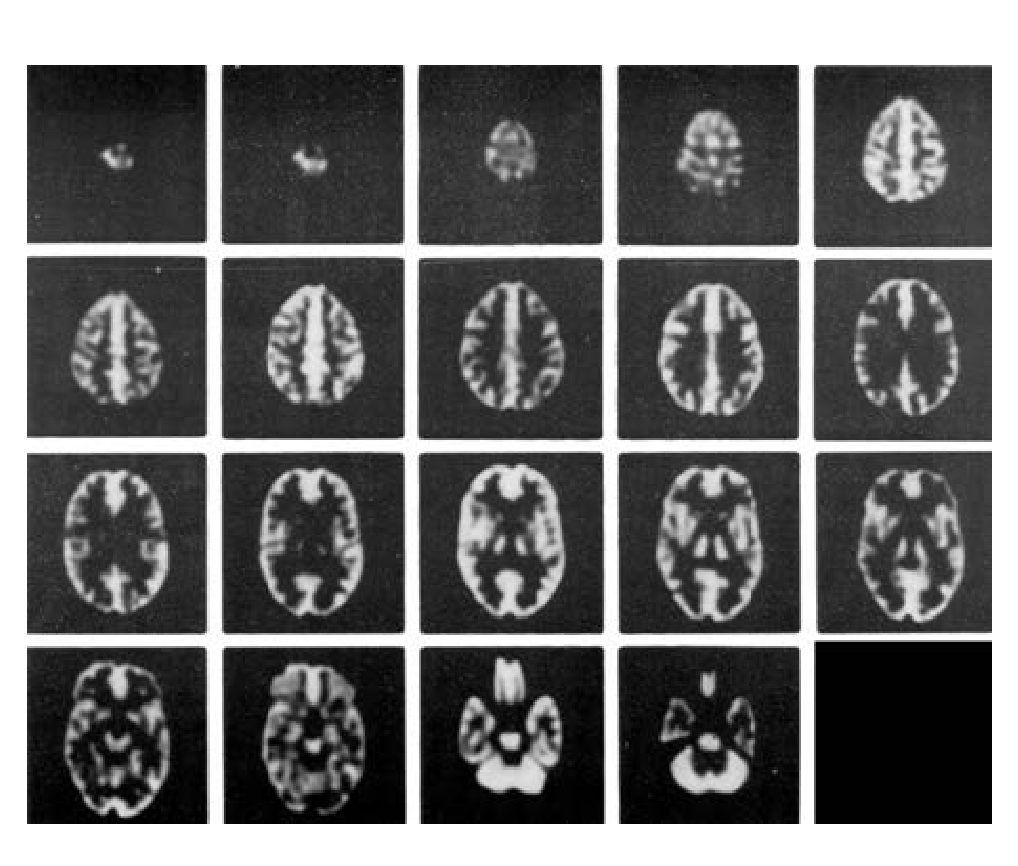

在脑部SPECT及脑部PET的研究中,从解剖学角度精确的模拟放射性分布;

在MRI研究中,精确模拟质子密度及驰豫参数的分布。

● 在血流和代谢研究中模拟正常灰质和白质的 4:1 摄取率(按部分体积效应模拟)。

可用于脑部ECT研究中对图像获取及重建方法的评估

3D重建方法评估

3D衰减及散射补偿方法评估

3D,SPECT,PET及MRI系统配准技术评估